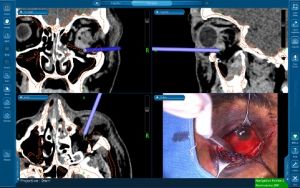

Use of technology for improved outcomes

The use of intra-operative image guidance(navigation surgery)[15] (figure 12) and prebending implants on 3D printed skull models[13] for implant customisation can help improve surgical outcomes.